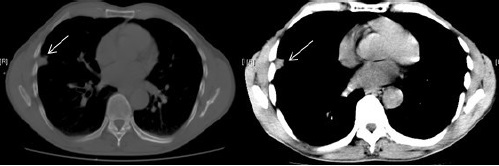

Se indicó tomografía computarizada (TC) tóraco-abdominal con contraste en la que se confirmó la presencia de un nódulo pulmonar subpleural situado en el segmento lateral del lóbulo medio, de 19 mm, contornos irregulares, descartarse se trate de un carcinoma pulmonar (Figura 2).

Se recomendó punción aspirativa con aguja fina (PAAF). No adenopatías mediastínicas, ni hiliares. En la PAAF del nódulo pulmonar no se obtienen hallazgos histopatológicos concluyentes de carcinoma de pulmón. Se remitió a cirugía torácica que realizó tratamiento quirúrgico: lobectomía pulmonar derecha, donde el resultado del estudio anatomopatológico de la lesión fue una neumonía.